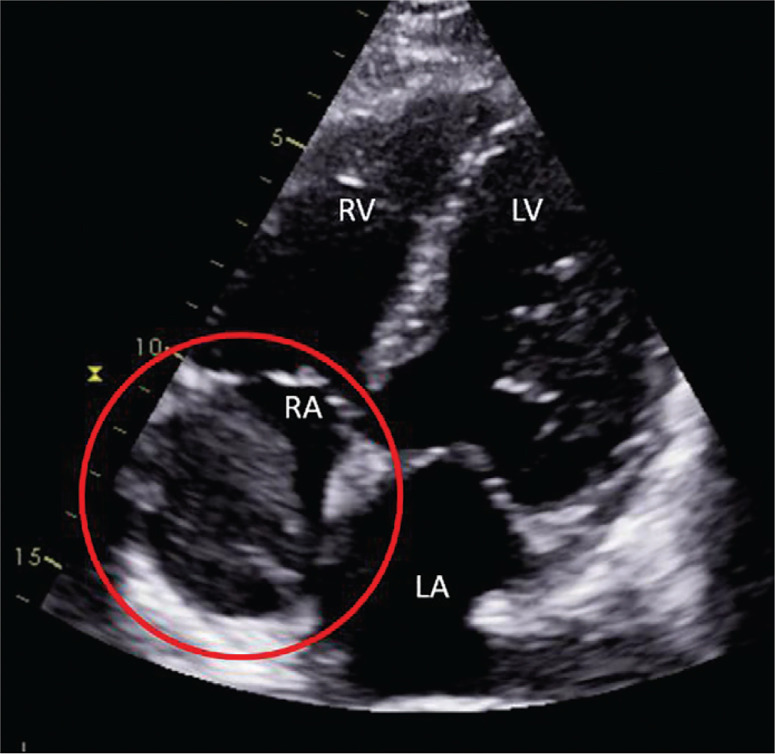

We report a case of an uncommonly aggressive presentation of the rare entity of synchronous papillary (PTC) and follicular thyroid carcinomas (FTC) in a 67-year-old female initially presenting with thyrotoxicosis from Graves' disease. She was found to have two thyroid nodules with extensive intra-cardiac tumour thrombus, symptomatic left pelvis bony metastasis with pathological fracture, pulmonary metastases and mediastinal lymph node metastases. Further investigations suggested a diagnosis of synchronous papillary and metastatic follicular thyroid cancer. Treatment with radical surgery followed by adjuvant therapeutic radioiodine ablation was proposed, but the patient declined all forms of cancer-specific therapy and was elected solely for a palliative approach to treatment. We discuss the diagnostic considerations in arriving at the diagnosis of synchronous thyroid malignancy - in this case the clear features of PTC and the strong probability of FTC due to invasiveness and metastatic follicular lesions. This case underscores potential limitations of the ACR TI-RADS system, notably with certain ultrasonographic features suggesting malignancy that might not be adequately captured. Notably, the aggressive presentation of DTC in this case may be contributed by the concurrent presence of Graves' Disease, suggesting heightened vigilance when assessing potential thyroid malignancies in such patients.